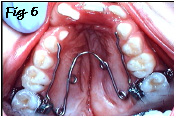

Avant de "souder" , avec une greffe osseuse, les deux segments du maxillaire séparés par la fente alvéolaire, on aura donc parfois avantage à tenter une expansion palatine à l'aide d'un appareil comme le QUADHELIX (ressort fixé sur deux bagues, Fig.6) ou une plaque palatine avec vérin, suivant les cas.